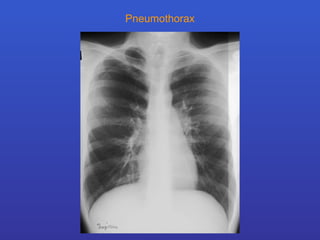

Pneumothorax